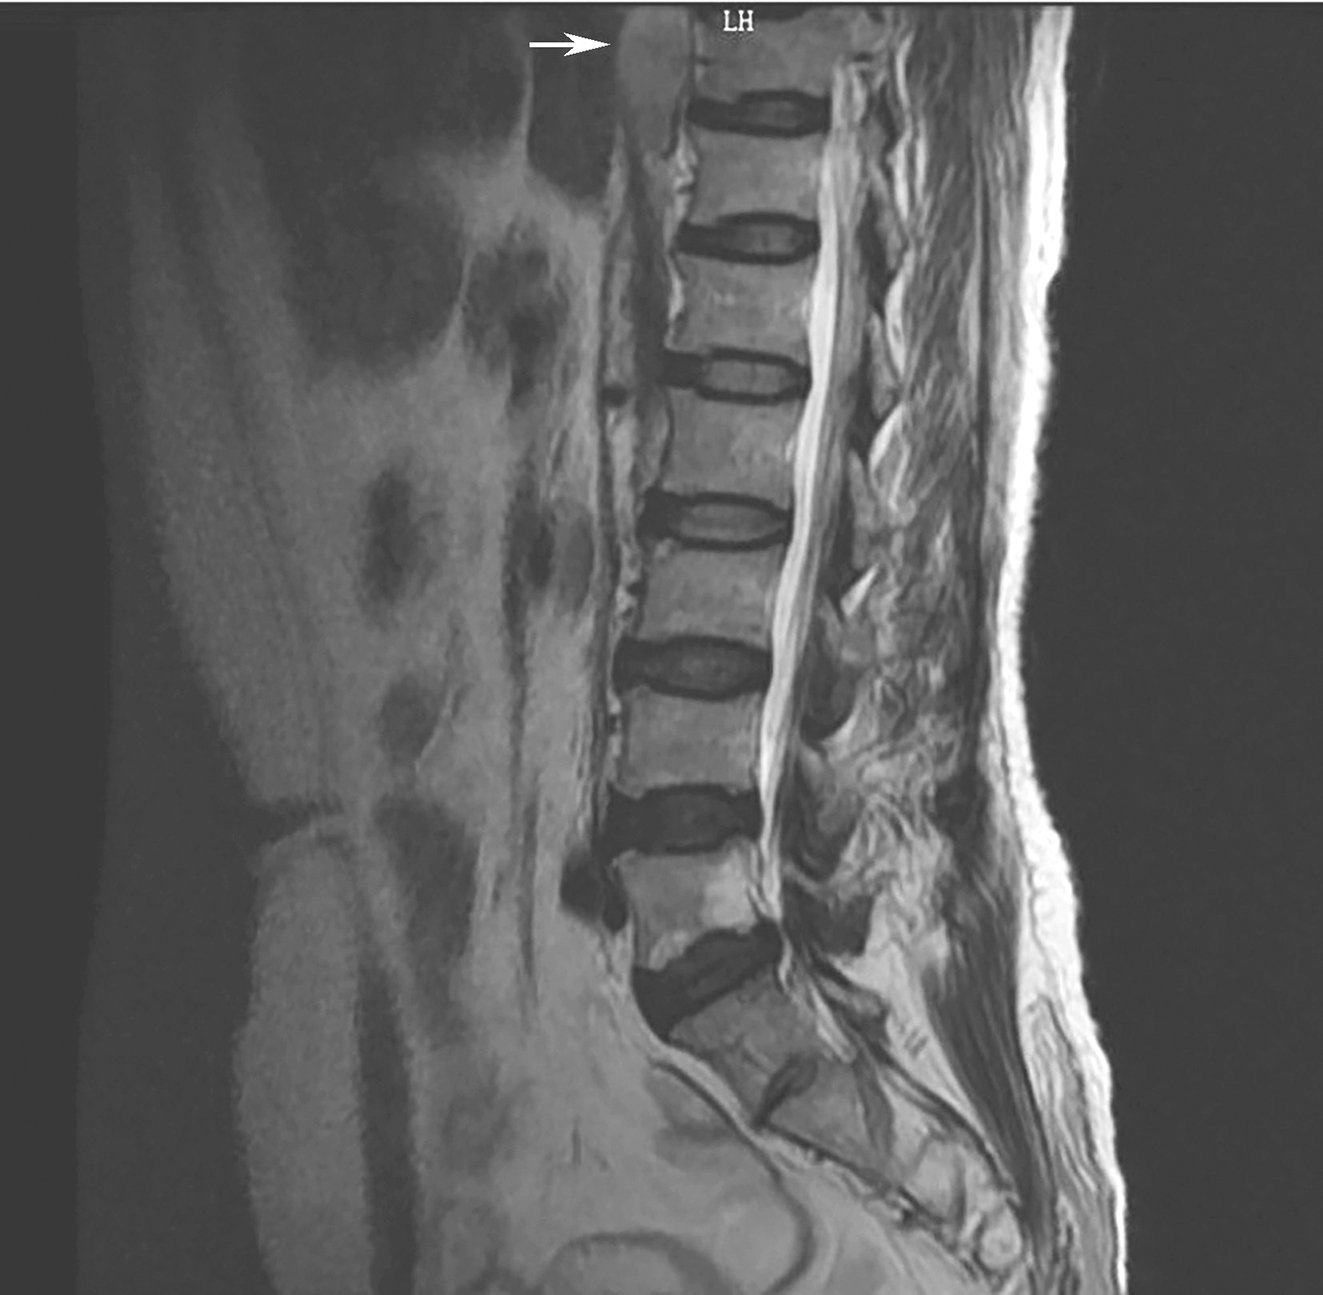

腰椎MRI平扫(图3):①腰椎退行性改变,L3/L 4、L4/L5椎间盘变性膨出,L5/S1椎间盘变性突出,后方椎管变窄;②S1腰化可能,L5椎体局部黄髓化;③约T11~T12水平脊柱前缘占位,神经源性肿瘤首先考虑;④骶尾部后方肌肉信号影,请结合临床。

图3腰椎MRI提示胸椎前方结节

引自:胃肠间质瘤典型病例诊治与解析.第1版.ISBN:978-7-117-30146-6.主编:陶凯雄 曹 晖